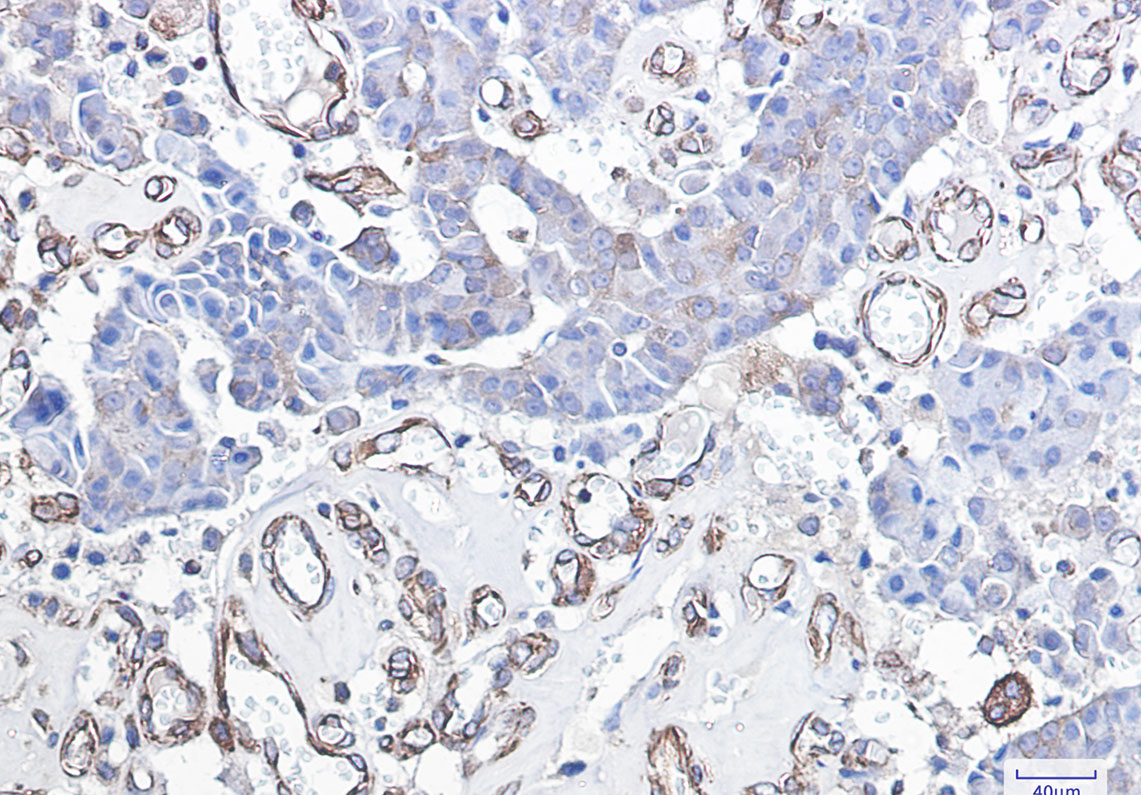

Product Image

- Immunohistochemistry analysis of paraffin-embedded Human breast cancer using DDIT3 antibody. High-pressure and temperature Sodium Citrate pH 6.0 was used for antigen retrieval.